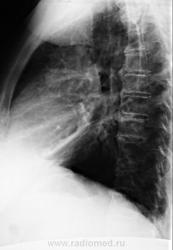

По рентгенографии органов грудной клетки в легких не менее 4 образований... Поскольку живем не в юго-восточной Азии с паразитами, предполагаем в первую очередь метастазы.

Из истории заболевания - оперирована по "женски" чуть больше 1 года назад, получала лучевую терапию....(гинекологи в направлении пишут рак влагалища..